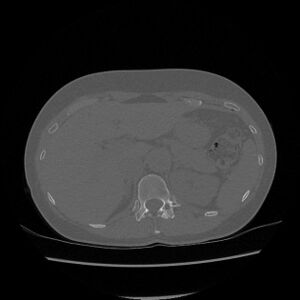

- CT – used mainly before MR, nowadays it is definitely not an imaging method of first choice in the field of spinal tumor diagnostics [8]. However, it can be performed as an additional examination, most often in extradural spinal tumors for imaging of calcifications, mineralizations, etc. [9]

Spinal osteoid osteomas in the vast majority cause painful scoliosis, concavely on the lesion side, vertebral deformities create compression on the spinal cord. The therapy is surgical, or radiofrequency ablation is used. [13][14] náhled|CT – spinální osteoblastom

Osteoblastoma[edit | edit source]

Osteoblastoma is also a benign tumor that occurs predominantly in younger patients and is characterized by its local aggressiveness. It is typically significantly vascularized, unlike osteoid osteoma, does not contain an osteosclerotic margin, otherwise they are histologically very similar. Osteoblastoma occurs in spongiosis, usually exceeding the size of 2 cm. [15][16][17]

The incidence of spinal osteoblastomas is approximately 40% of all osteoblastomas, most often occurring in the cervical area, they also cause very painful back pain associated with scoliosis. The procedure of therapy is more or less identical to osteoid osteoma. [18]